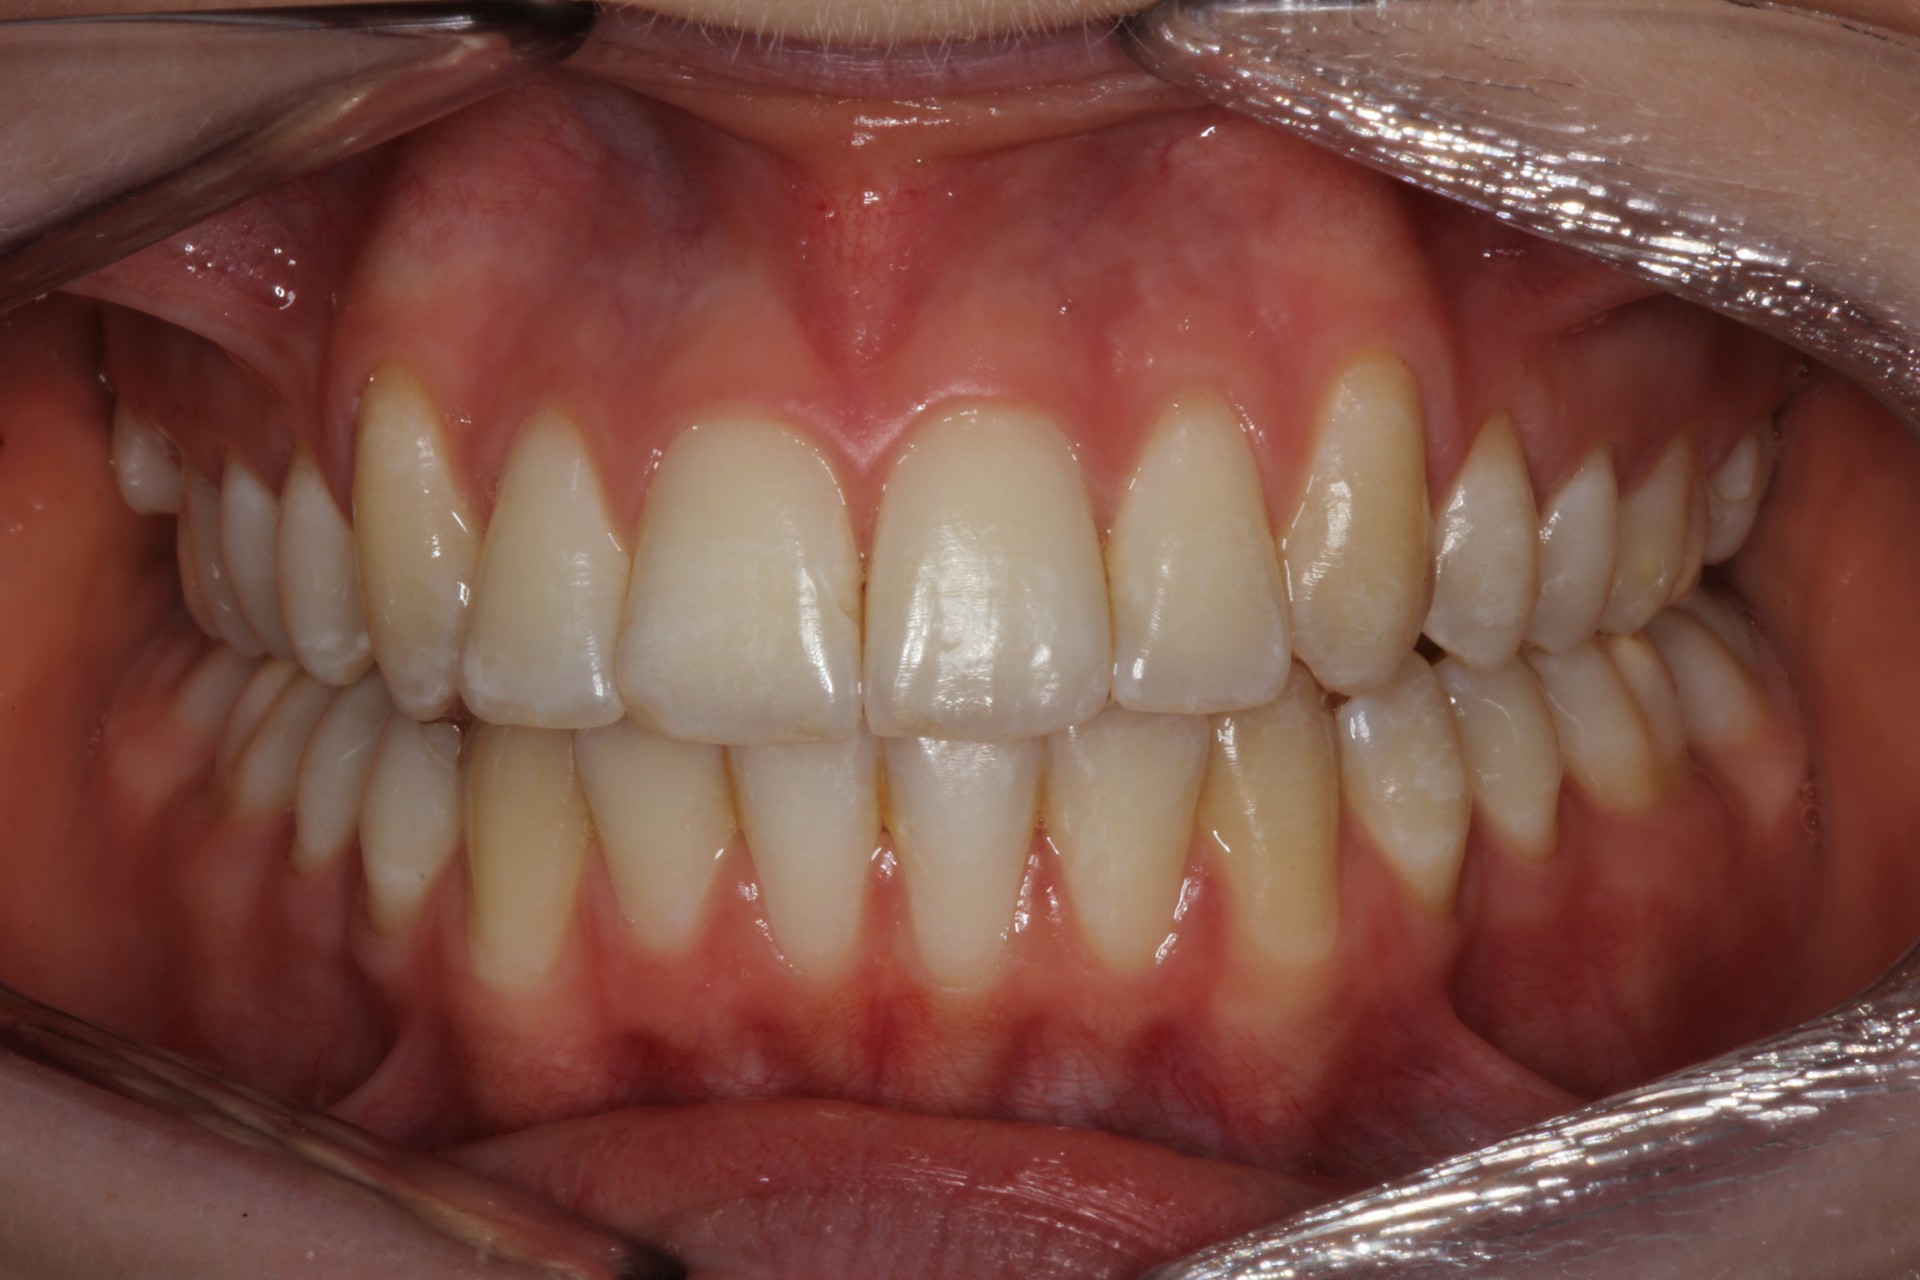

Protruding front teeth – Child case